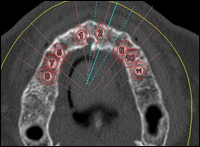

Fig 2 & 3: A DentaScan was taken to assess the maxilla in 3-dimensions. Eight dental implants were placed in the virtual image of the maxilla using Simplant software.